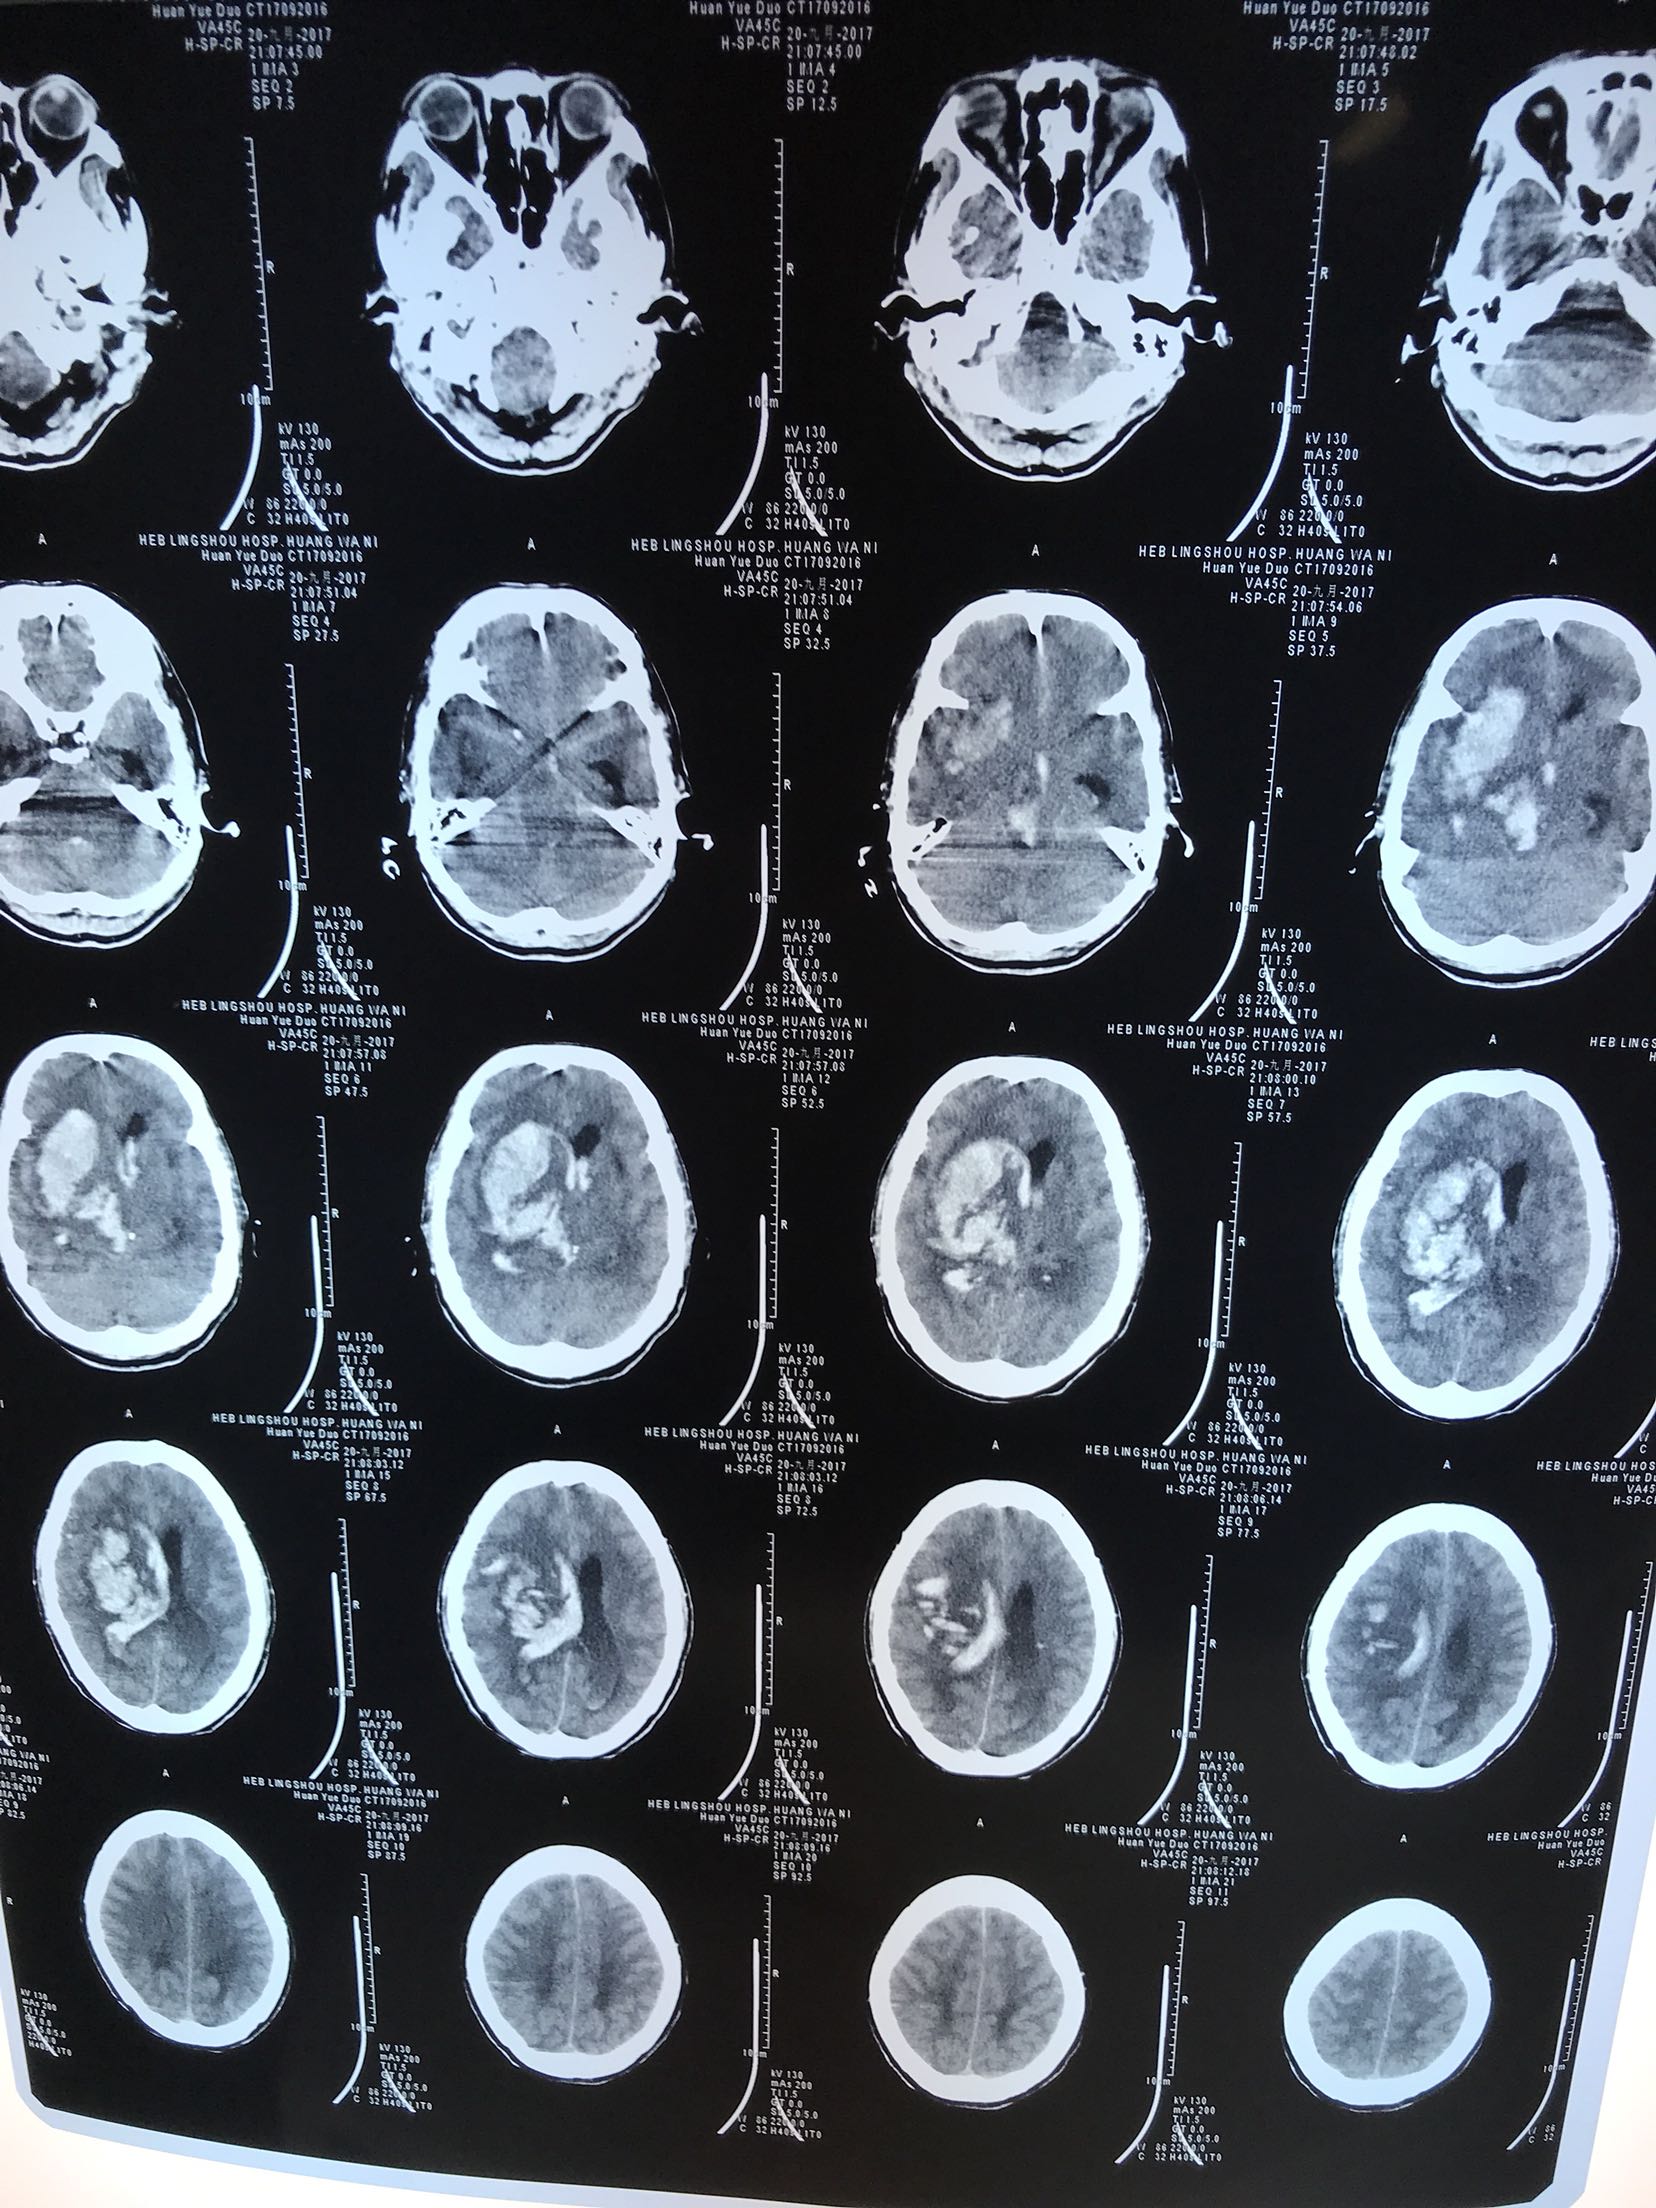

突发意识不清2小时,既往高血压,未口服过药物2小时前患者突发意识不清,急诊急查头CT:右侧基底节丘脑出血破入脑室,脑疝,为进一步治疗收住院

体温35.9℃ 脉搏50次/分 血压180/110mmhg,意识模糊,双侧瞳孔正大等圆,对光反射灵敏,双肺呼吸音粗,未闻及干湿性啰音,心音有力各瓣膜听诊区未闻及杂音,腹软肝脾未触及,肠鸣音正常,双下肢无水肿,四肢肌力不清,双侧巴氏征阳性

大面积脑出血 脑疝 高血压3级 极高危,家属拒绝手术,给于保护脑神经,脱水降颅压等治疗

患者经治疗2天,仍意识不清,血压低,去甲肾上腺素维持血压。